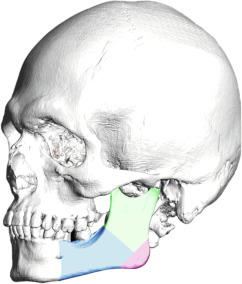

Jaw and Chin Complex

To better understand the jaw, it needs to be divided into the mandibular body, the mandibular angle and the ascending ramus ( Fig. 8.3 ). Generally speaking, the male jaw is larger, with greater body height and a broader ascending ramus. The mandibular angle formed by the body and ramus tends to be more acute in males, at times with everted gonial angles. The greater bone volume and vertical height are important factors when planning mandibular reshaping techniques in FGCS.

The male chin tends to be more square-shaped, with more pronounced and defined transitions between the chin and mandibular body, greater bone volume, and a more significant vertical dimension. Gender does not necessarily determine the position of the chin; that is, it is possible to find retro-positioned or over-projected chins in both men and women. However, a well-defined and projected chin may improve the overall aesthetics of the jaw-chin region.